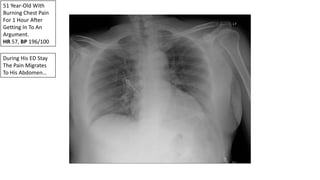

51 Year-Old With

Burning Chest Pain

For 1 Hour After

Getting In To An

Argument.

HR 57, BP 196/100

During His ED Stay

The Pain Migrates

To His Abdomen…

Aortic Dissection

• Aortic dissection